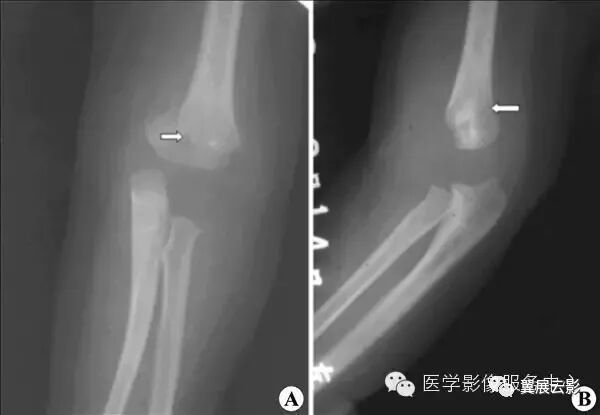

【影像表现】:X线正、侧位(A、B)示肱骨髁上骨质断裂,远侧断段向背侧移位(↑)。【影像诊断】:肱骨髁上骨折。

【影像表现】:X线肘关节正位(A)及侧位(B)示骨折向前成角,远折端向后移位。【影像诊断】:肱骨髁上骨折伸直型。